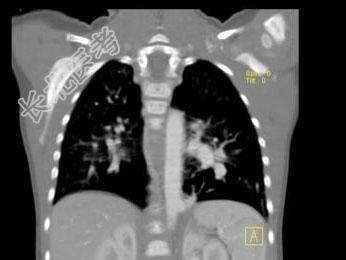

- 单项选择题女,2岁, 咳嗽,结合图像, 最可能的诊断是 ( )

A、先天性肺不张

B、细支气管肺炎

C、先天性支气管闭锁

D、先天性囊性腺瘤样畸形

E、肺隔离症